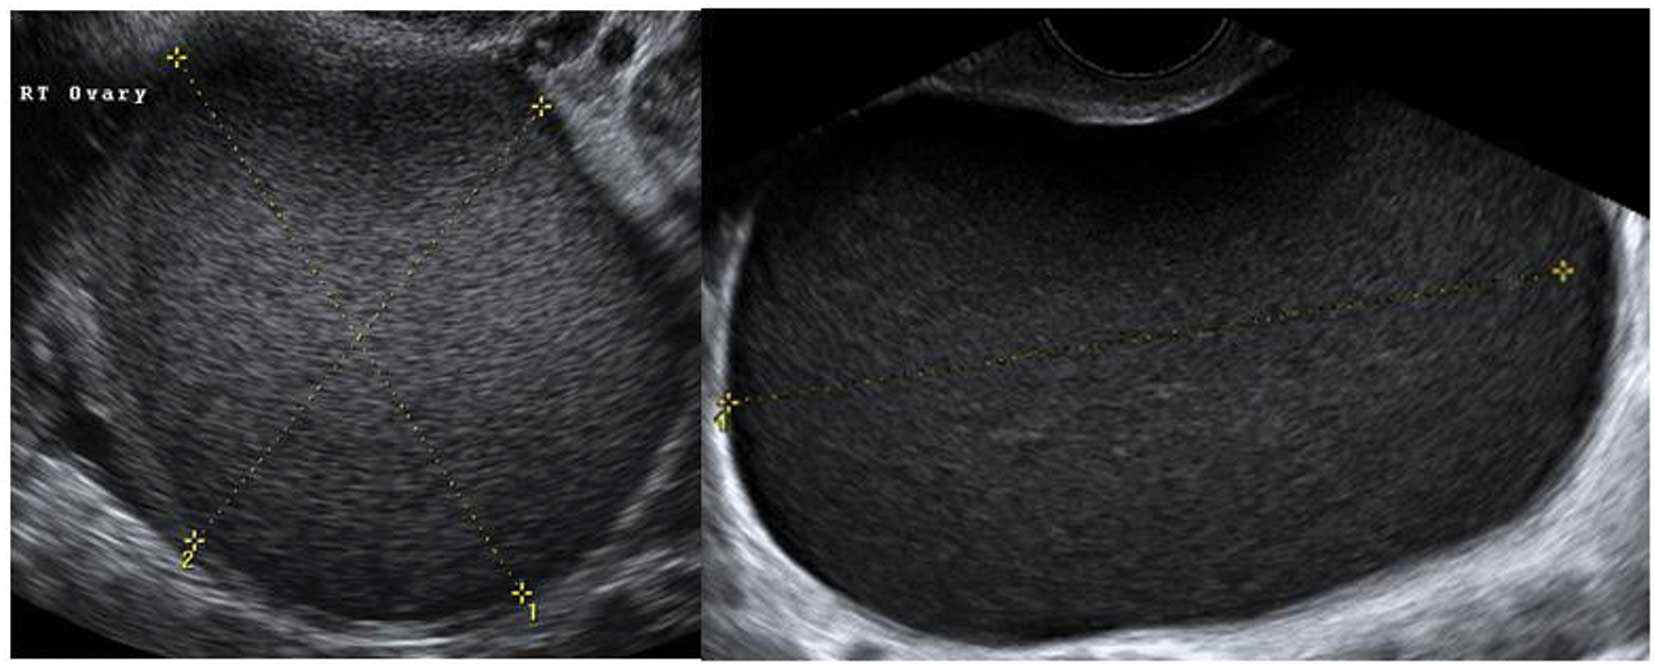

Endometriomas

Ultrasonography is particularly sensitive for accurately diagnosing ‘typical’ endometriomas, most commonly seen in premenopausal women. Typically an endometrioma is a unilocular tumor and has low-level echogenicity representing old blood in the cyst cavity (commonly termed ‘ground glass’). It is this ‘ground glass’ feature that is the most typical feature (28,31–33) (Fig. 15).

Figure 15

Typical endometriomas.